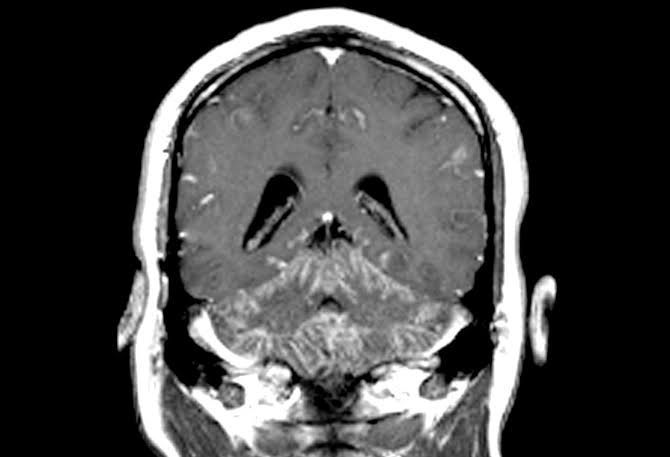

Neurosarcoidosis is characterized by inflammation and abnormal cell deposits in any part of the nervous system—the brain, spinal cord, or peripheral nerves. It most commonly occurs in the cranial and facial nerves, the hypothalamus (a specific area of the brain), and the pituitary gland.